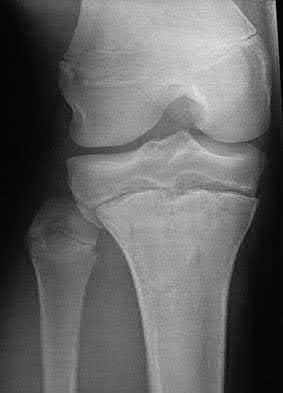

Figure A is an AP radiograph of a posterior knee dislocation. Figure B is a lateral showing the same injury.